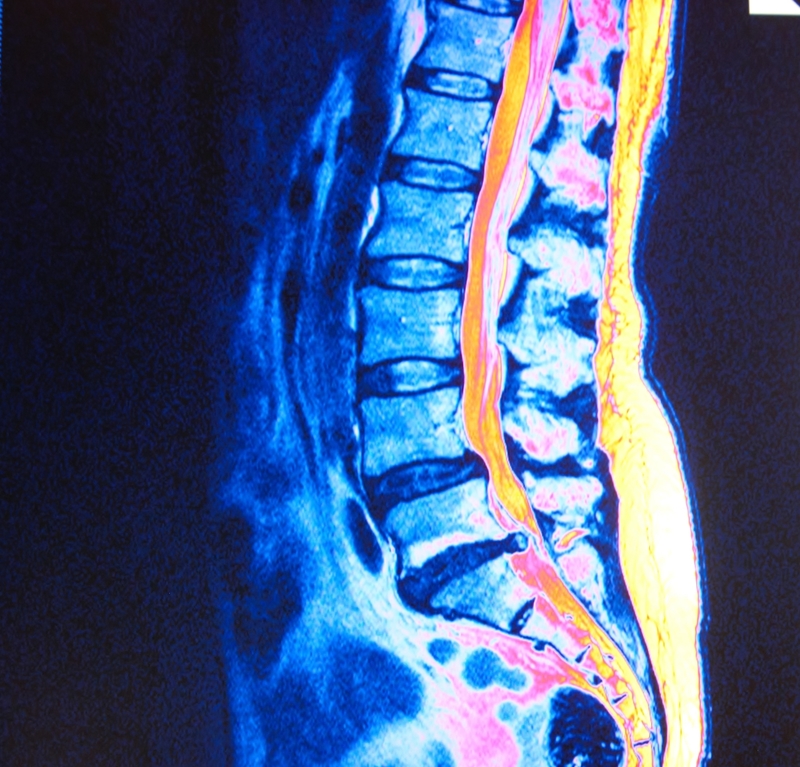

Lumbar Spinal Stenosis

Lumbar spinal stenosis is a condition describing the narrowing of the area in the lower spine responsible for carrying nerves to the lower extremities. This area is very small, and it becomes even smaller when surrounding bone and tissue grows. Accidents, arthritis, and general wear and tear on the spinal bones and joints play a significant role in lumbar spinal stenosis. When the lumbar canal is restricted, the nerves traveling through it become squeezed, resulting in back pain as well as leg pain and weakness. Many adults knowingly and unknowingly suffer from this form of stenosis.

Sciatica

Back conditions, such as sciatica, often lead to leg pain as well. Sciatica is an inflammation of the sciatic nerve, which begins in your lower back and travels down to your legs and feet. While sciatica can be difficult to diagnose and its symptoms sometimes diminish on their own, it is often the result of spinal stenosis. Sciatica and other spinal conditions may develop gradually, or they may come on suddenly. Much of the time, what once was tolerable turns into an acute issue. Arthritis or injury can lead to an acute development of sciatica as well.